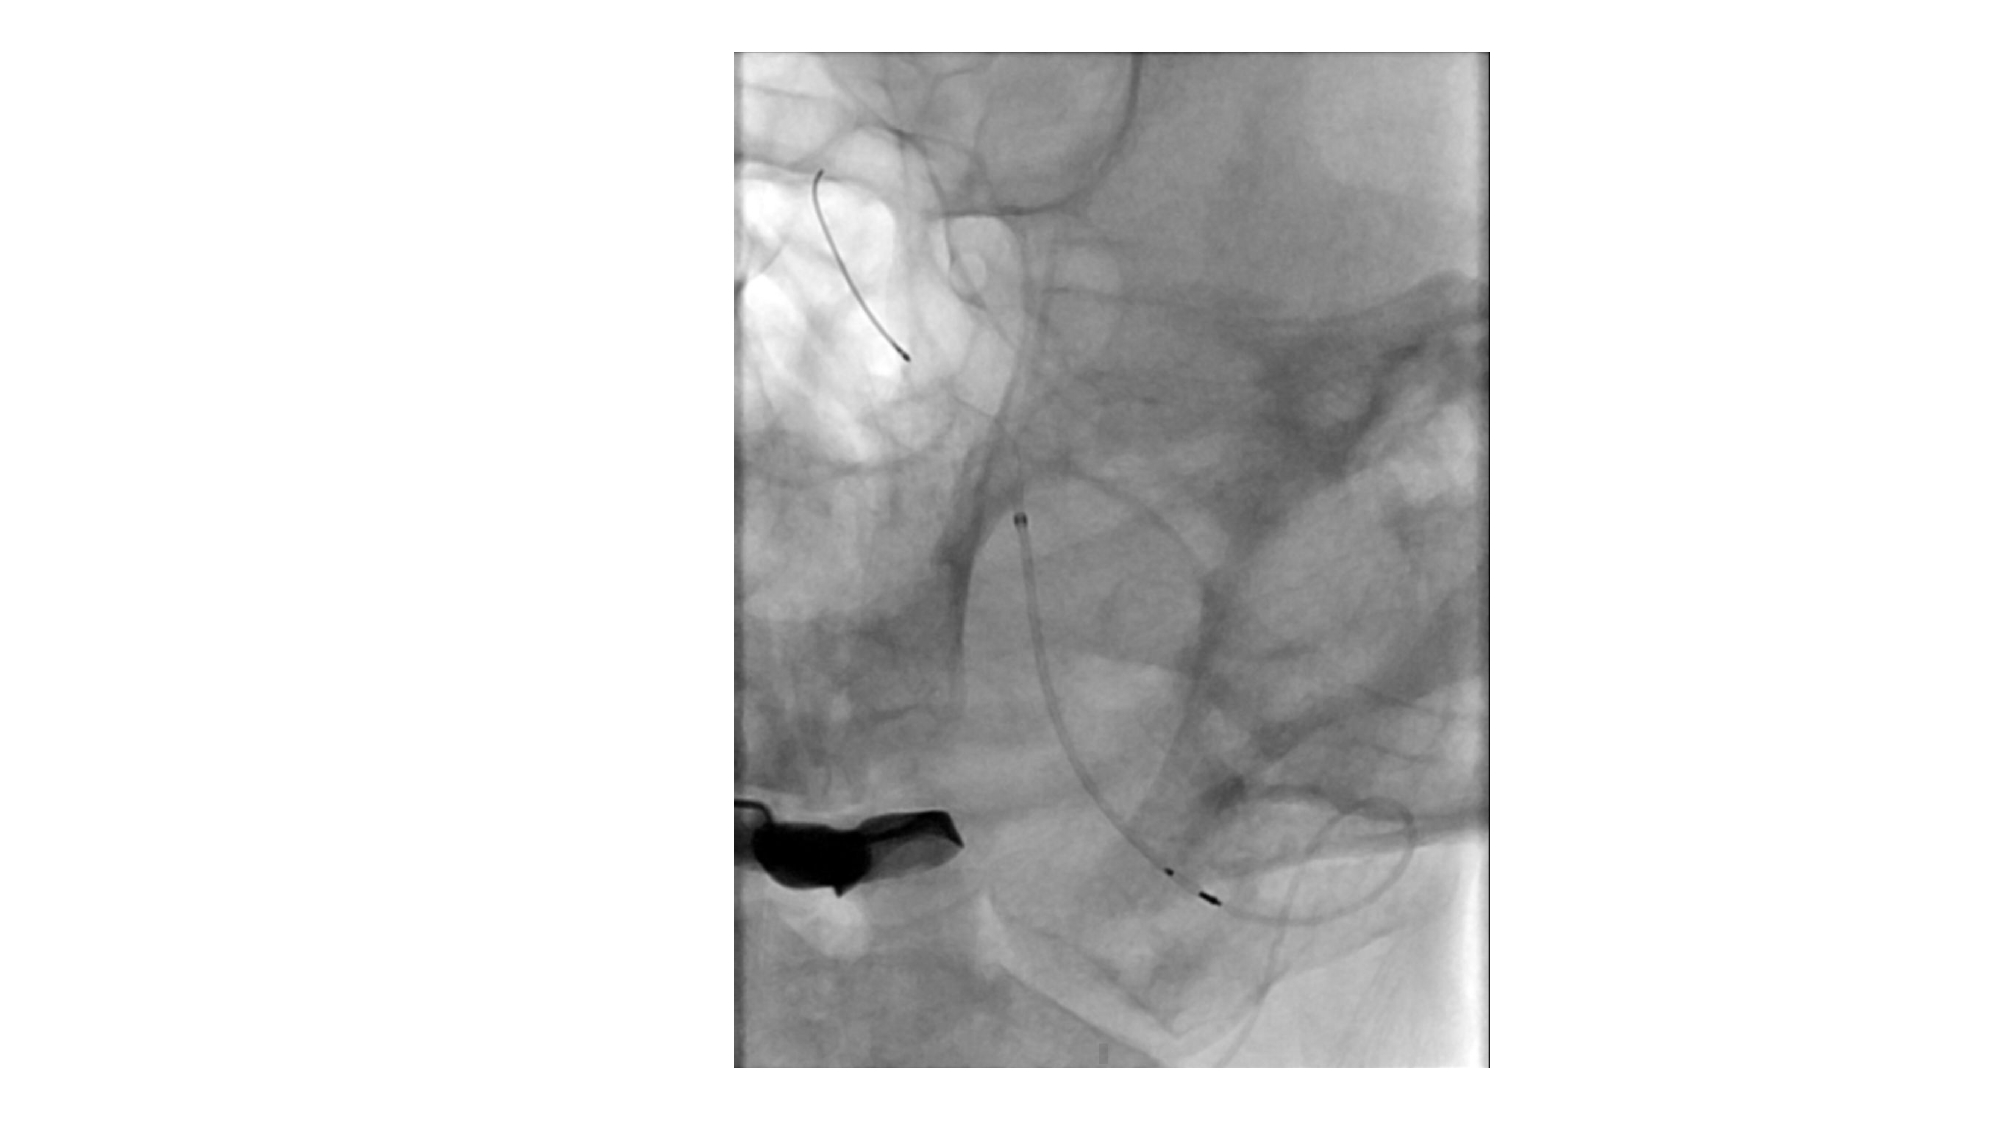

| 14:10 - 15:10 | DEBATE 2 | Recurrent chronic subdural hematoma– surgical or endovascular intervention? Surgical: Assoc. Prof. Duong Dai Ha Endovascular: Assoc. Prof. Le Thanh Dung | Moderator: Prof. Christian Matula Assoc. Prof. Duong Dai Ha | |

| 15:10 - 16:10 | Interactive Case Demonstration and Discussion II: ~20 minutes each, (5 minutes presentation followed by 15 minutes discussion) Practicals: How I am doing it? Participants present case presentations about how they do it? The faculty comment on and discussion. 1. Endoscopic approach in post-traumatic CSF leakage - Dr. Nguyen Thanh Xuan 2. Endovascular approach in CCF - Assoc. Prof. Le Thanh Dung | Prof. Christian Matula International & local faculties Participants | |